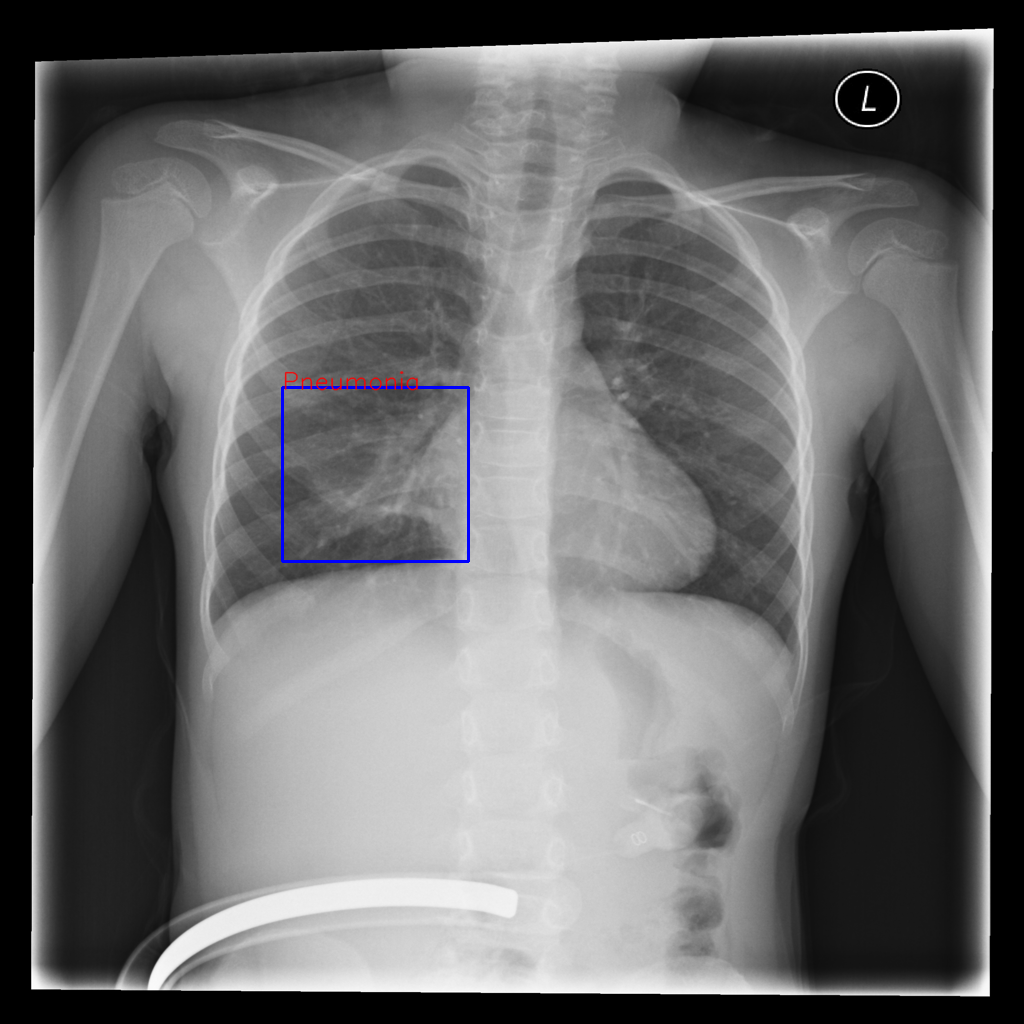

Refer to caption

Figure 1: Overview of MedVistaGym, which contains a comprehensive suite of reasoning-intensive medical image analysis tasks and tools in an interactive execution environment, scaling visual-centric tool-integrated agentic reinforcement learning for VLM agents.

MedVistaGym comprises a set of verifiable medical VQA tasks that demand grounded, multi-step reasoning over visual inputs and intermediate evidence. These tasks span diverse diagnostic scenarios, including clinical perception, lesion-level evidence localization, subtle abnormality detection, and diagnosis-oriented evidence aggregation, where generating reliable answers requires calling external tool support. The training data in MedVistaGym is organized along two complementary axes. (1) Radiology VQA, covering cross-sectional and projection imaging, includes VQA-RAD Lau et al. (2018), which focuses on anatomy and finding recognition in X-ray, CT, and MRI images, and SLAKE Liu et al. (2021), a knowledge-aware dataset with clinically grounded questions over diverse radiology images. (2) Pathology VQA, covering microscopy and histopathology, includes PathVQA He et al. (2020), which emphasizes cellular morphology and tissue patterns. More details are provided in Appendix A.2.

To support grounded medical image verifiable analysis, MedVistaGym exposes a standardized and extensible suite of executable tools that enable agents to offload perception, localization, segmentation, and knowledge retrieval. These tools return structured outputs that can be directly used as intermediate evidence during reasoning. The tools used in MedVistaGym are organized into four complementary families: (1) Resolution and Region Refinement, which enable focused inspection of image regions (e.g., agent4k, zoom-in); (2) Medical Localization and Segmentation support the detection and delineation of anatomical or pathological regions (e.g., groundingdino, medsam2); (3) Medical Visual Understanding and Parsing, providing a structured interpretation of medical images (e.g., biomedclip, biomedparse); (4) External Biomedical Knowledge Retrieval enables access to curated medical knowledge sources (e.g., GoogleSearch, DrugBank, PubMed). See Appendix E for tool details.